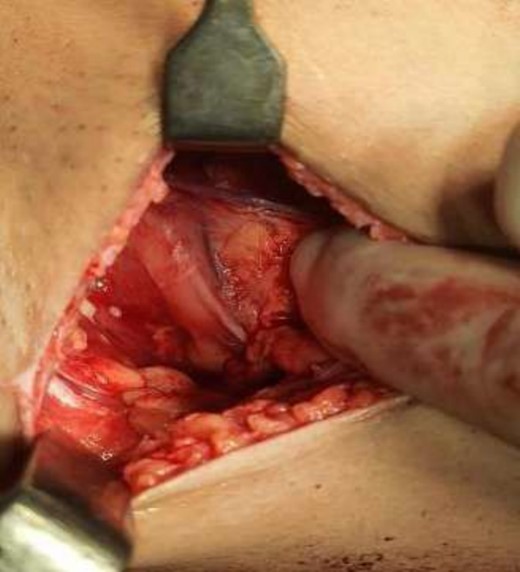

The operating surgeon opted for a vertical mastopexy to remove the mass and simultaneously reconstruct the breast to restore it as much as possible and to have a cosmetically better scar (Fig. 7). The skin was marked, a peri-areolar ellipse having a diameter of about 15 cm was made that extended vertically below, 4 cm above the inframammary fold. The skin was dissected along the incision line and the mass was removed. Grossly, the specimen measuring 5 × 3.5 × 3 cm3, containing the firm mass, was sent for histopathological analysis. Axillary lymph node biopsy was done. Two drains were placed, and the skin was closed in the form of a superior circle and an inferior ellipse (Figs 3–6).

Mastectomy procedure (Elliptical Incision given around nipple).

Mastectomy along with sentinel lymph node biopsy procedure (Tumor Approach).